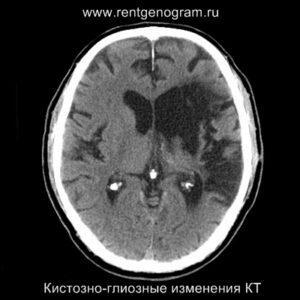

Хроническая фаза (более 6 недель)

В хроническом периоде наблюдаются процессы репарации и пролиферации, что ведет к обратному развитию вазогенного отека и восстановлению ГЭБ, что проявляется полным отсутствием контрастного усиления в зоне поражения. В местах энцефаломаляции формируются ликворные кисты (лакунарный инсульт) или происходят кистозно-глиозные изменения. Также фиксируется снижение кровотока или полная окклюзия артерии в области инфаркта.

Может начать происходить гибель аксонов нейронов, входящих в пирамидный тракт (дегенерация Тюрка-Валлера), создавая выраженную зону глиоза, которая повторяет ход пирамидного тракта. Высокий МР-сигнал на DWI полностью исчезает. Зона кистозно-глиозных изменений может приводить к тракционной дилатации полостей, что вызывает асимметричное растяжение желудка, прилегающего к зоне глиоза (гидроцефалия ex-vacuo).